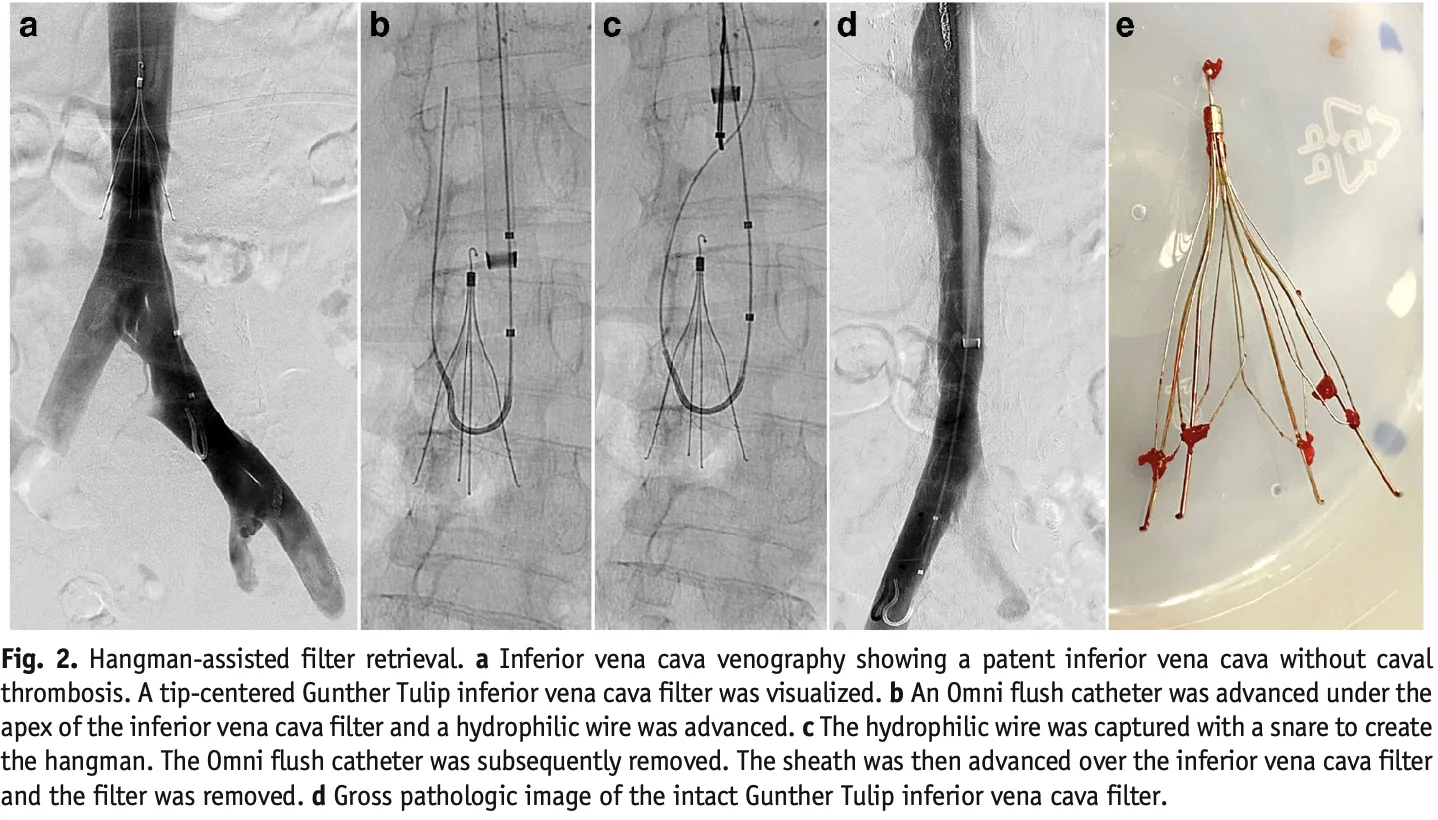

フィルターは, 傘の骨のような構造で, 血管の中で拡がり, 血栓が肺に流れていくのを防ぎます.

しかし, 総腸骨静脈には血栓が残存していたため, 明後日, 心臓血管外科で下大静脈フィルターを留置してもらう方針となりました.